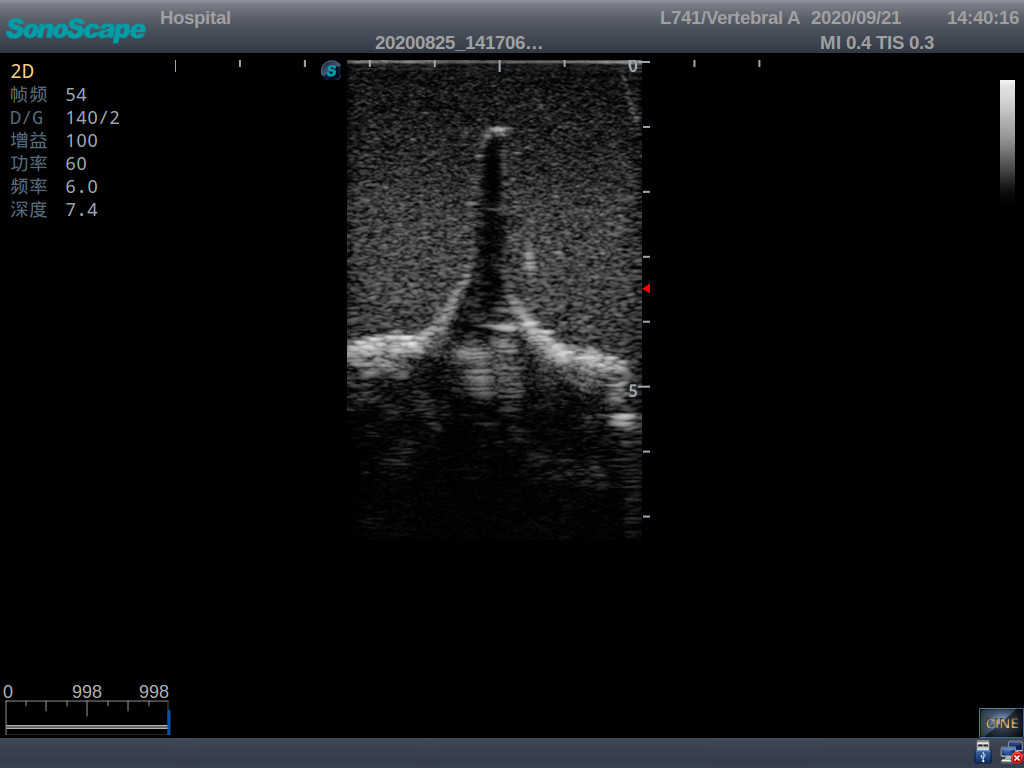

2) Real clinical ultrasound images

1) Ultrasound-guided lumbar puncture practice